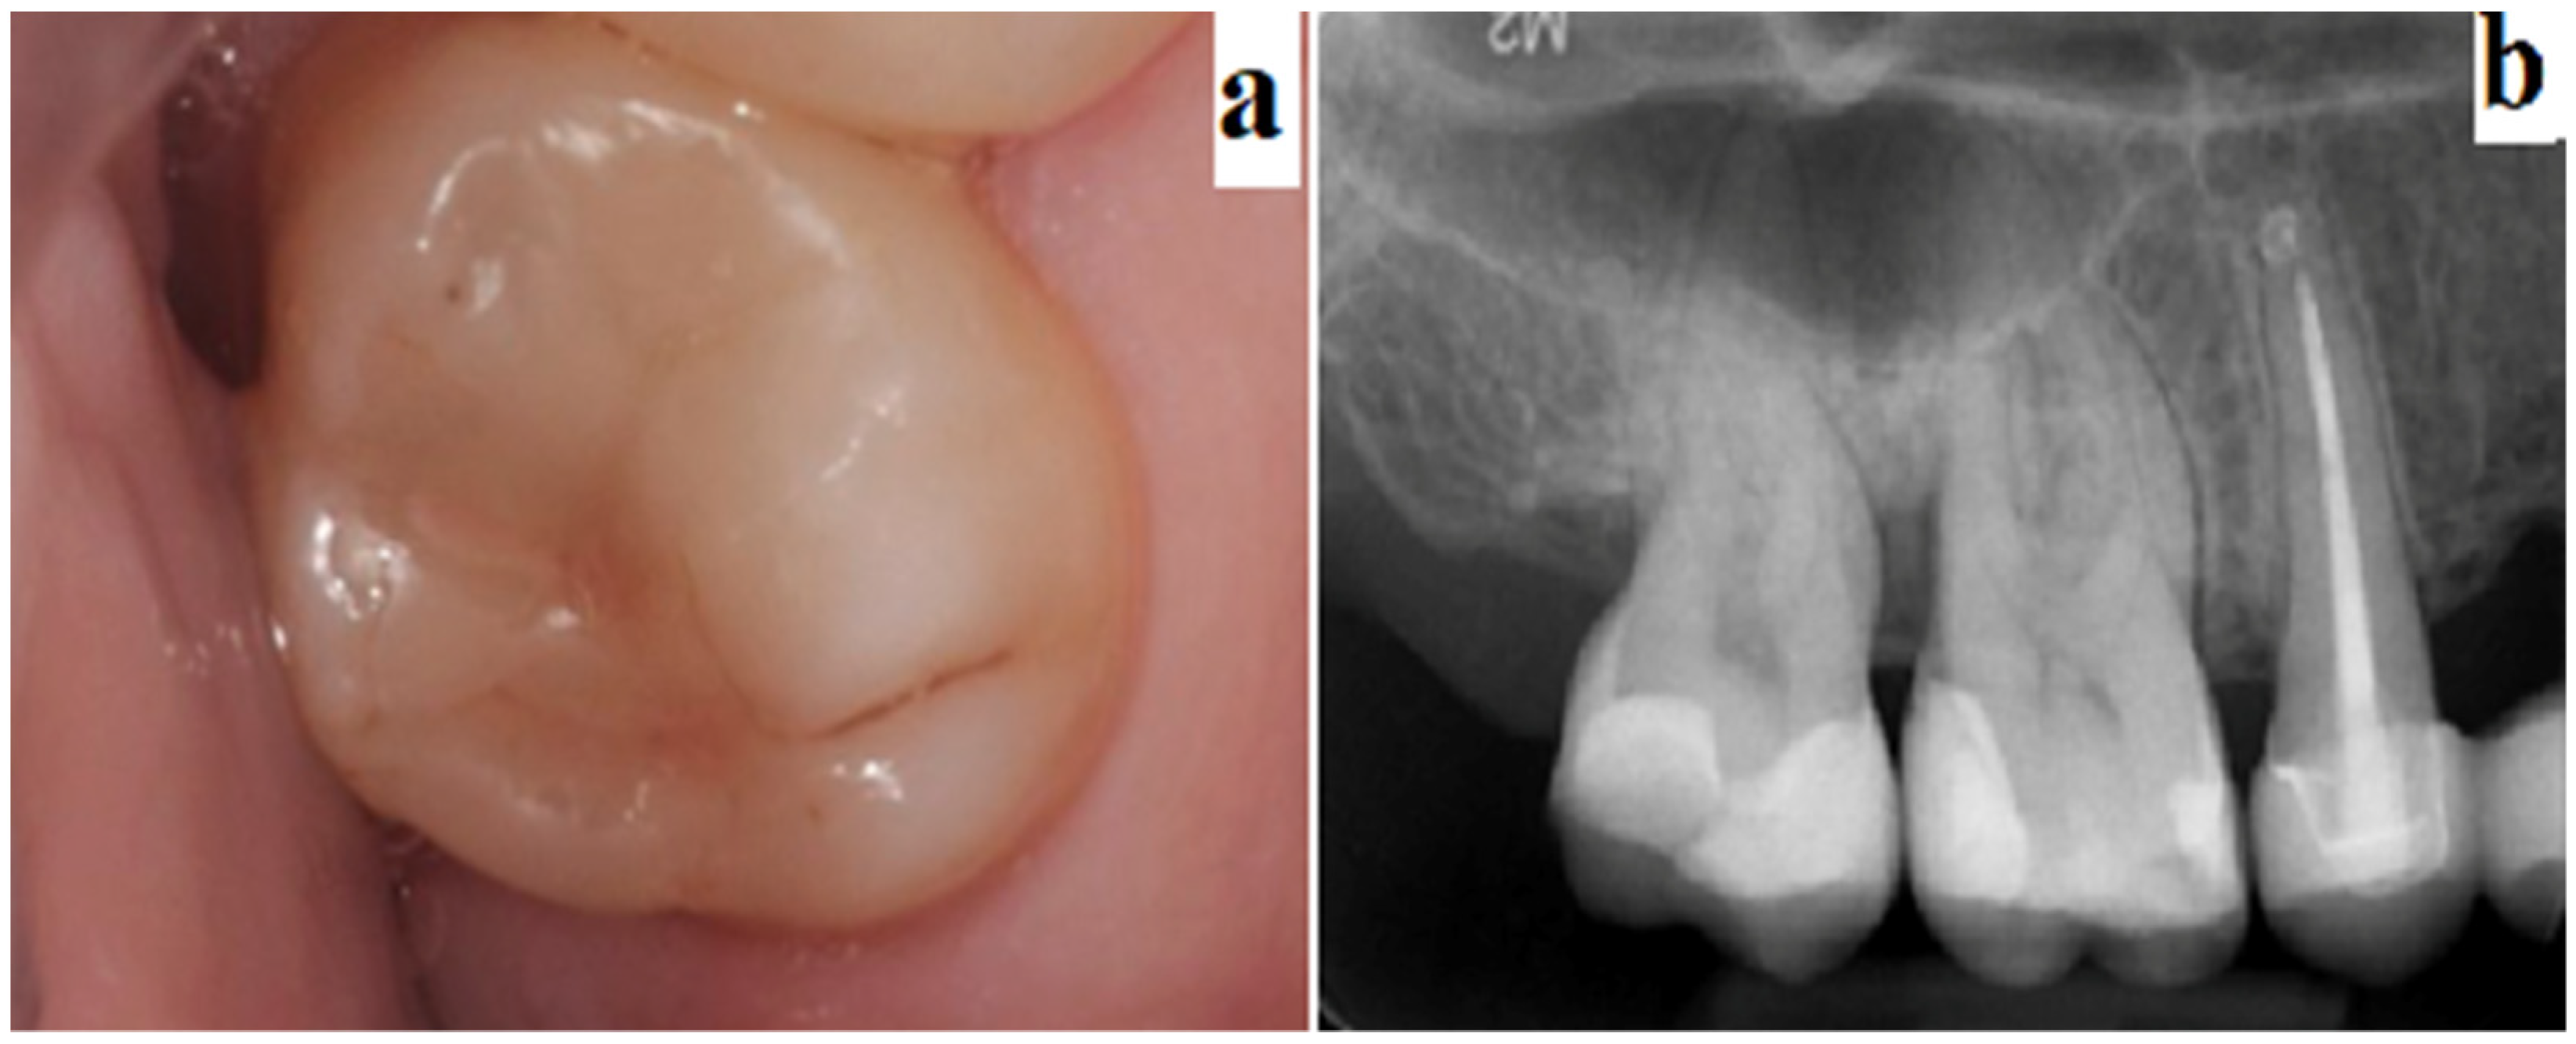

One month, 3 months, and 6 months after treatment, clinical controls were performed. During these periodical controls, qualitative tests were performed such as the pulp vitality test, which included the vertical and horizontal percussion tests (see Figure 1).

Figure 1.

Example of evaluation 6 months post-op: Clinical evaluation—marginal infiltration (a); periapical X-ray evaluation (b).

Therapies on teeth that remained asymptomatic, with normal sensitivity tests and no other radiographic signs, such as periapical pathology, were considered as clinical successes.